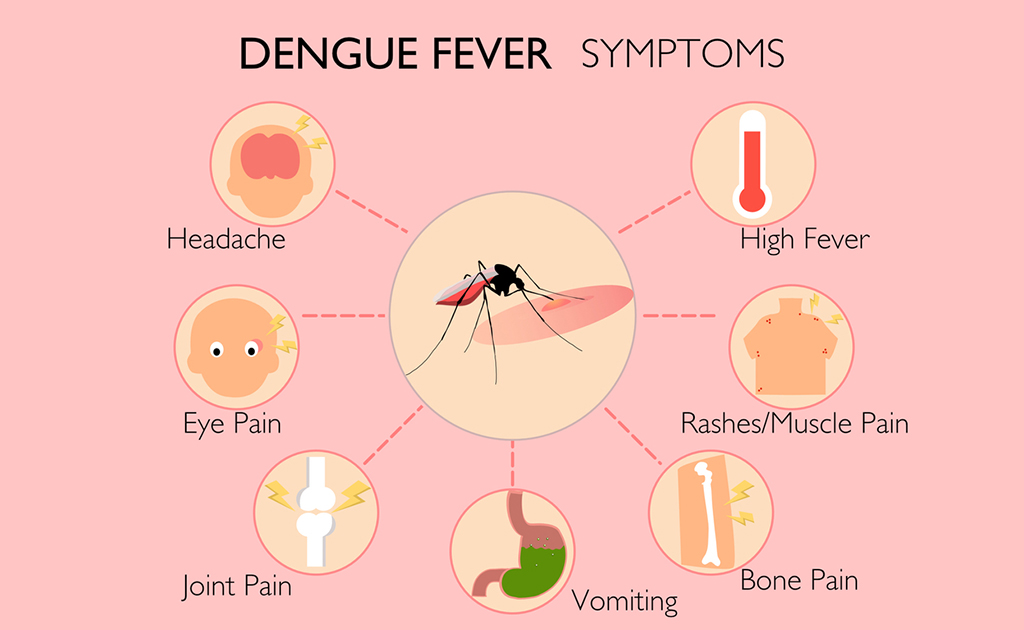

ডেঙ্গুতে আক্রান্ত হয়েছেন কিনা কোন লক্ষণগুলো দেখে বুঝবেন?

0 SHARES Share Tweet বর্তমানে সারাদেশে ডেঙ্গুর প্রাদুর্ভাব অনেক বেড়ে গেছে। সাম্প্রতিক বছরগুলোতে ক্রমবর্ধমান ডেঙ্গু জ্বরে...